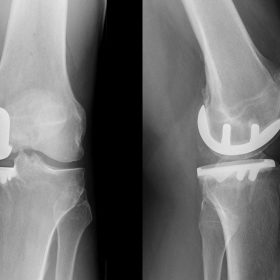

Διάγνωση- Σταδιοποίηση

Διακρίνονται σε 4 στάδια.

Στάδιο Ι. Στένωση του μεσαθριου διαστήματος

Στάδιο ΙΙ. Σκλήρυνση του υποκύμενου χόνδρου

Στάδιο ΙΙΙ. Σκλήρυνση του υπερκείμενου χόνδρου, καταστροφή του υποχόνδρινου οστούν, σχηματισμός οστεόφυτων, οίδημα αρθρώσεως και βραδυνός πόνος

Στάδιο IV. Οστική καθίζηση, καταστροφή μαλακών μορίων μυϊκών ομάδων, υπεξάρθρημα της αρθρώσεως και αλλαγή του μηχανικού άξονα